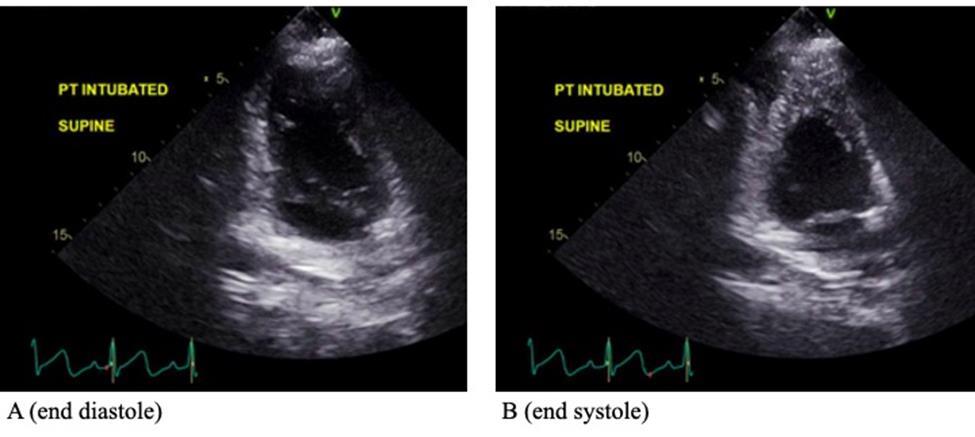

CARDIAC SARCOIDOSIS WITH PREDOMINANT RIGHT VENTRICLE INVOLVEMENT

Hannah Hart1, Devika Aggarwal1, Soumya Gupta1, Vikram Agarwal1, Isha Ranadive1

1Mount Sinai Morningside-West Hospitals, Icahn School of Medicine at Mount Sinai, New York, NY, United States

Presented at both the American College of Cardiology (ACC) Annual Meeting that was held in Atlanta, Georgia, United States from April 6-8, 2024 and the Annual Mount Sinai Health System Department of Medicine Research Day that was held in New York, New York, United States on May 6-7, 2024.